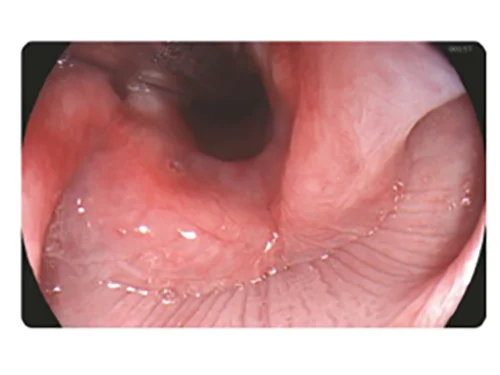

Белый свет

HEI

HEI: Улучшенная визуализация гемоглобина

Сочетание узкополосного красного, зеленого и желтого цветов улучшает видимость глубоких кровеносных сосудов и точек кровотечения за счет использования алгоритма слияния изображений и технологии автоматической обработки.

Применение

- Выявление кровотечений (упрощает остановку интраоперационных кровотечений)

- Визуализация варикозно расширенных вен для проведения лечения (упрощает обнаружение целевых вен при инъекционном лечении или перевязке вен).